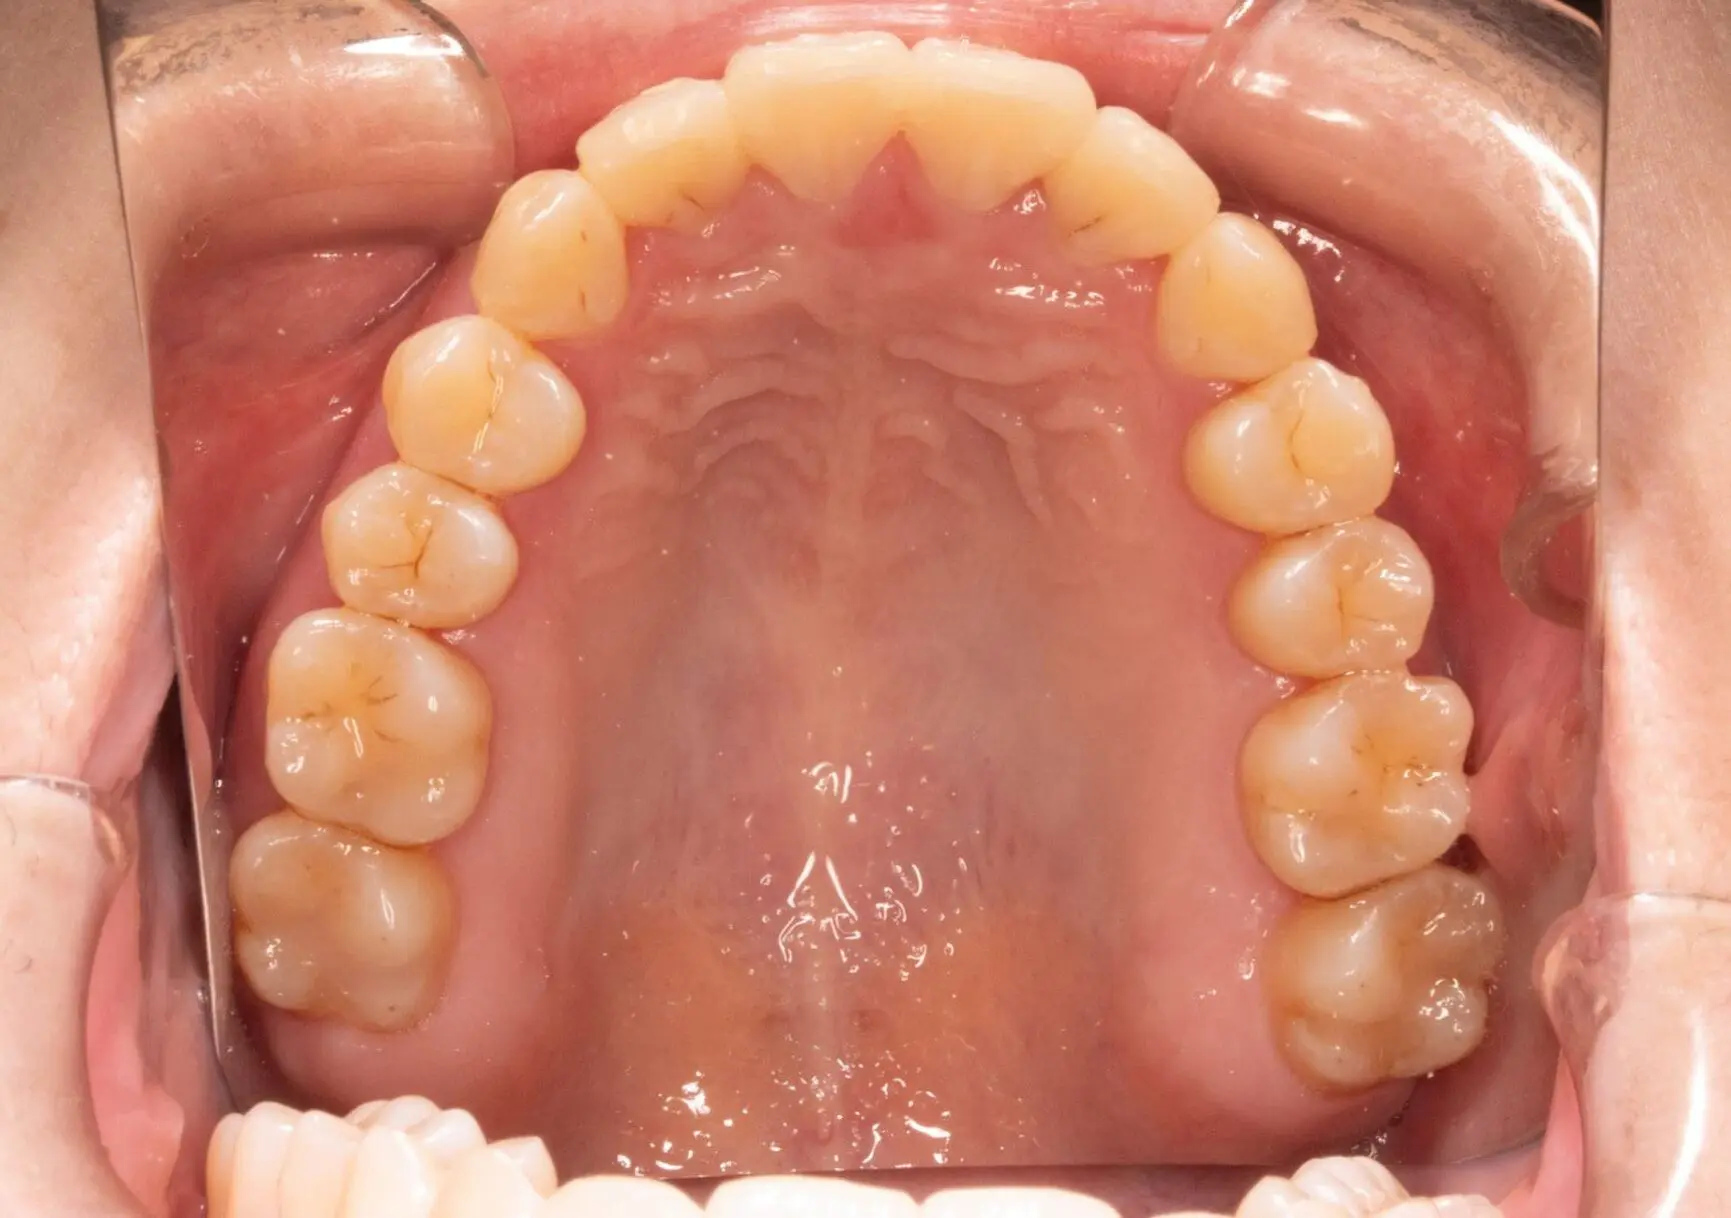

Before

After